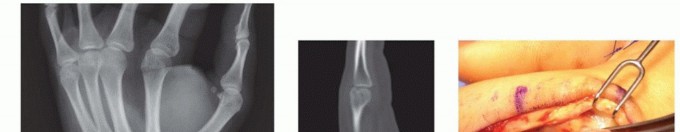

IMAGING AND OTHER DIAGNOSTIC STUDIES

The posteroanterior (PA) view can show shortening, especially relative to the adjacent metacarpals. Fracture angulation can be seen on the lateral view but is often best seen on the oblique view. Fractures of the base of the fifth metacarpal are best seen on the pronated oblique view.Specialized views of the metacarpal head can show the volar aspect (Brewerton) or the dorsal aspect (skyline).Traction views in the anesthetized patient may help elucidate pattern and extent of injury.Computed tomography (CT) scan can help in extensively comminuted fractures or articular injuries.